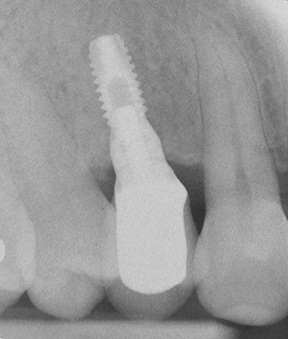

After removing fixation screws (Fig. 22), a 3.75 × 13 mm implant was placed with a final torque >35 N·cm (Figs. 23–24) and the flap was closed with 4-0 monofilament interrupted sutures (Fig. 25).

At the 24-month follow-up, a periapical X-ray was taken to assess the marginal peri-implant bone level, which was deemed satisfactory (Fig. 28).

Fig. 23: 3.75 × 13 mm implant placed (buccal view)

Block by Block

Fig. 28: Periapical radiograph at 24-month follow-up